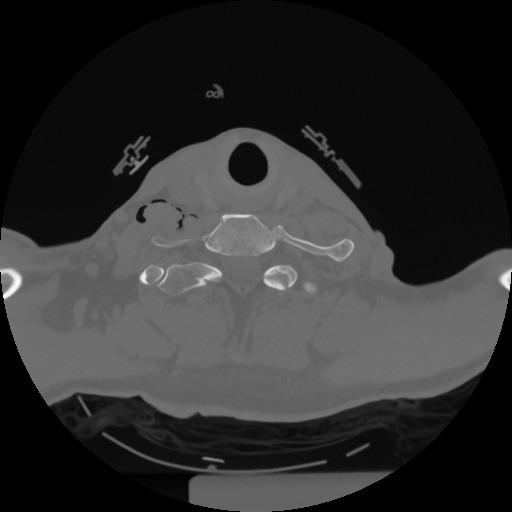

12 P.BLANDAS,,Vol,0.5,P.BLANDAS,,